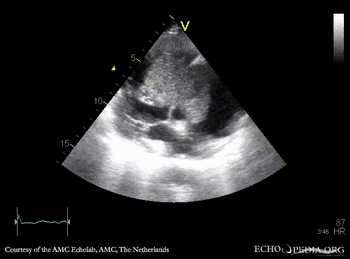

| Giant myxoma in right atrium

| PLAX: giant mobile myxoma in right atrium

PLAX